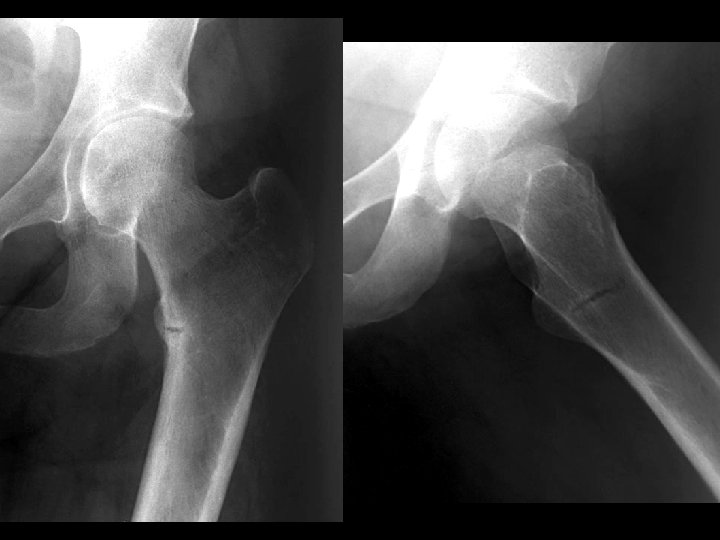

Femoral Head AVN • Findings: – bilateral femoral head AVN w/o collapse – right pelvic renal tx